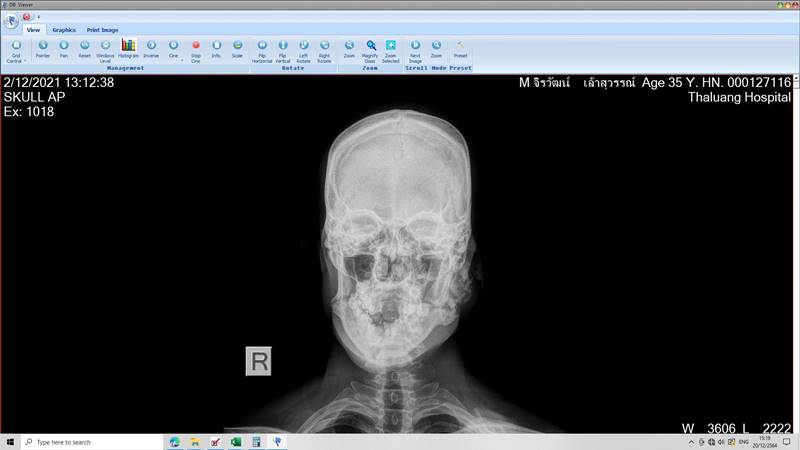

ล่าสุด (21 ธันวาคม 2564) ทนายเกิดผล แก้วเกิด โพสต์รูปและข้อความผ่านเฟซบุ๊ก เผยผลการเอกซเรย์ร่างกายของน้องฟ้าบางส่วน ซึ่งพบว่ามีร่องรอยกระดูกแตกหลายจุด โดยทนายชี้ว่า น้องฟ้าถูกเจ๊กั้ง นายอ้วน รวมถึงสามีของเจ๊กั้ง ร่วมกันทำร้ายร่างกายจนกระดูกแตกแต่ไม่ได้รับการรักษา ทำให้น้องฟ้าต้องทนทุกข์ทรมาน ปล่อยให้บาดแผลหายเองตามธรรมชาติ ซึ่งการที่ไม่ได้รับการรักษาและต่อกระดูกอย่างถูกต้อง ปล่อยให้กระดูกเชื่อมต่อเองตามธรรมชาตินั้น ทำให้การเชื่อมต่อของกระดูกผิดพลาด และร่างกายผิดรูป

"น้องฟ้าถูกทำร้ายจนกระดูกแตกหักทั่วร่างกาย ซ้ำ ๆ กัน หลาย ๆ ครั้ง ตั้งแต่หัวจรดปลายเท้า โดยไม่ได้รับการรักษาอย่างถูกต้อง คิดดูซิครับว่าจะทุกข์ทรมานแค่ไหน" ทนายเกิดผล ระบุ